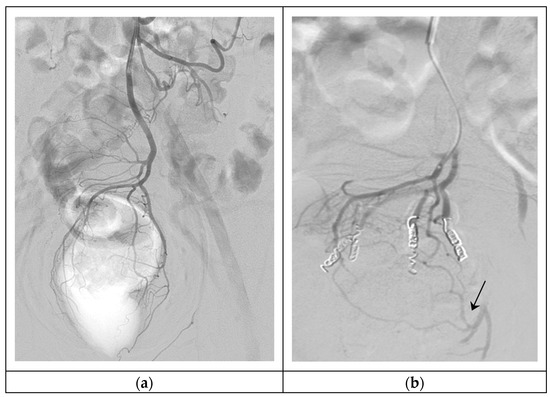

Hemorrhoids are blood cushions located in the anus and lower rectum, acknowledged as a common cause of bleeding, which can reduce quality of life. The development of minimally invasive techniques such as endovascular embolization of superior rectal artery, “Emborrhoid technique”, is an effective [...] Read more.

Hemorrhoids are blood cushions located in the anus and lower rectum, acknowledged as a common cause of bleeding, which can reduce quality of life. The development of minimally invasive techniques such as endovascular embolization of superior rectal artery, “Emborrhoid technique”, is an effective treatment, with no pain or ischemic complications, and allows quick patient recovery. Our purpose is to describe the general technique and discuss the results of the current literature. Full article

Figure 1